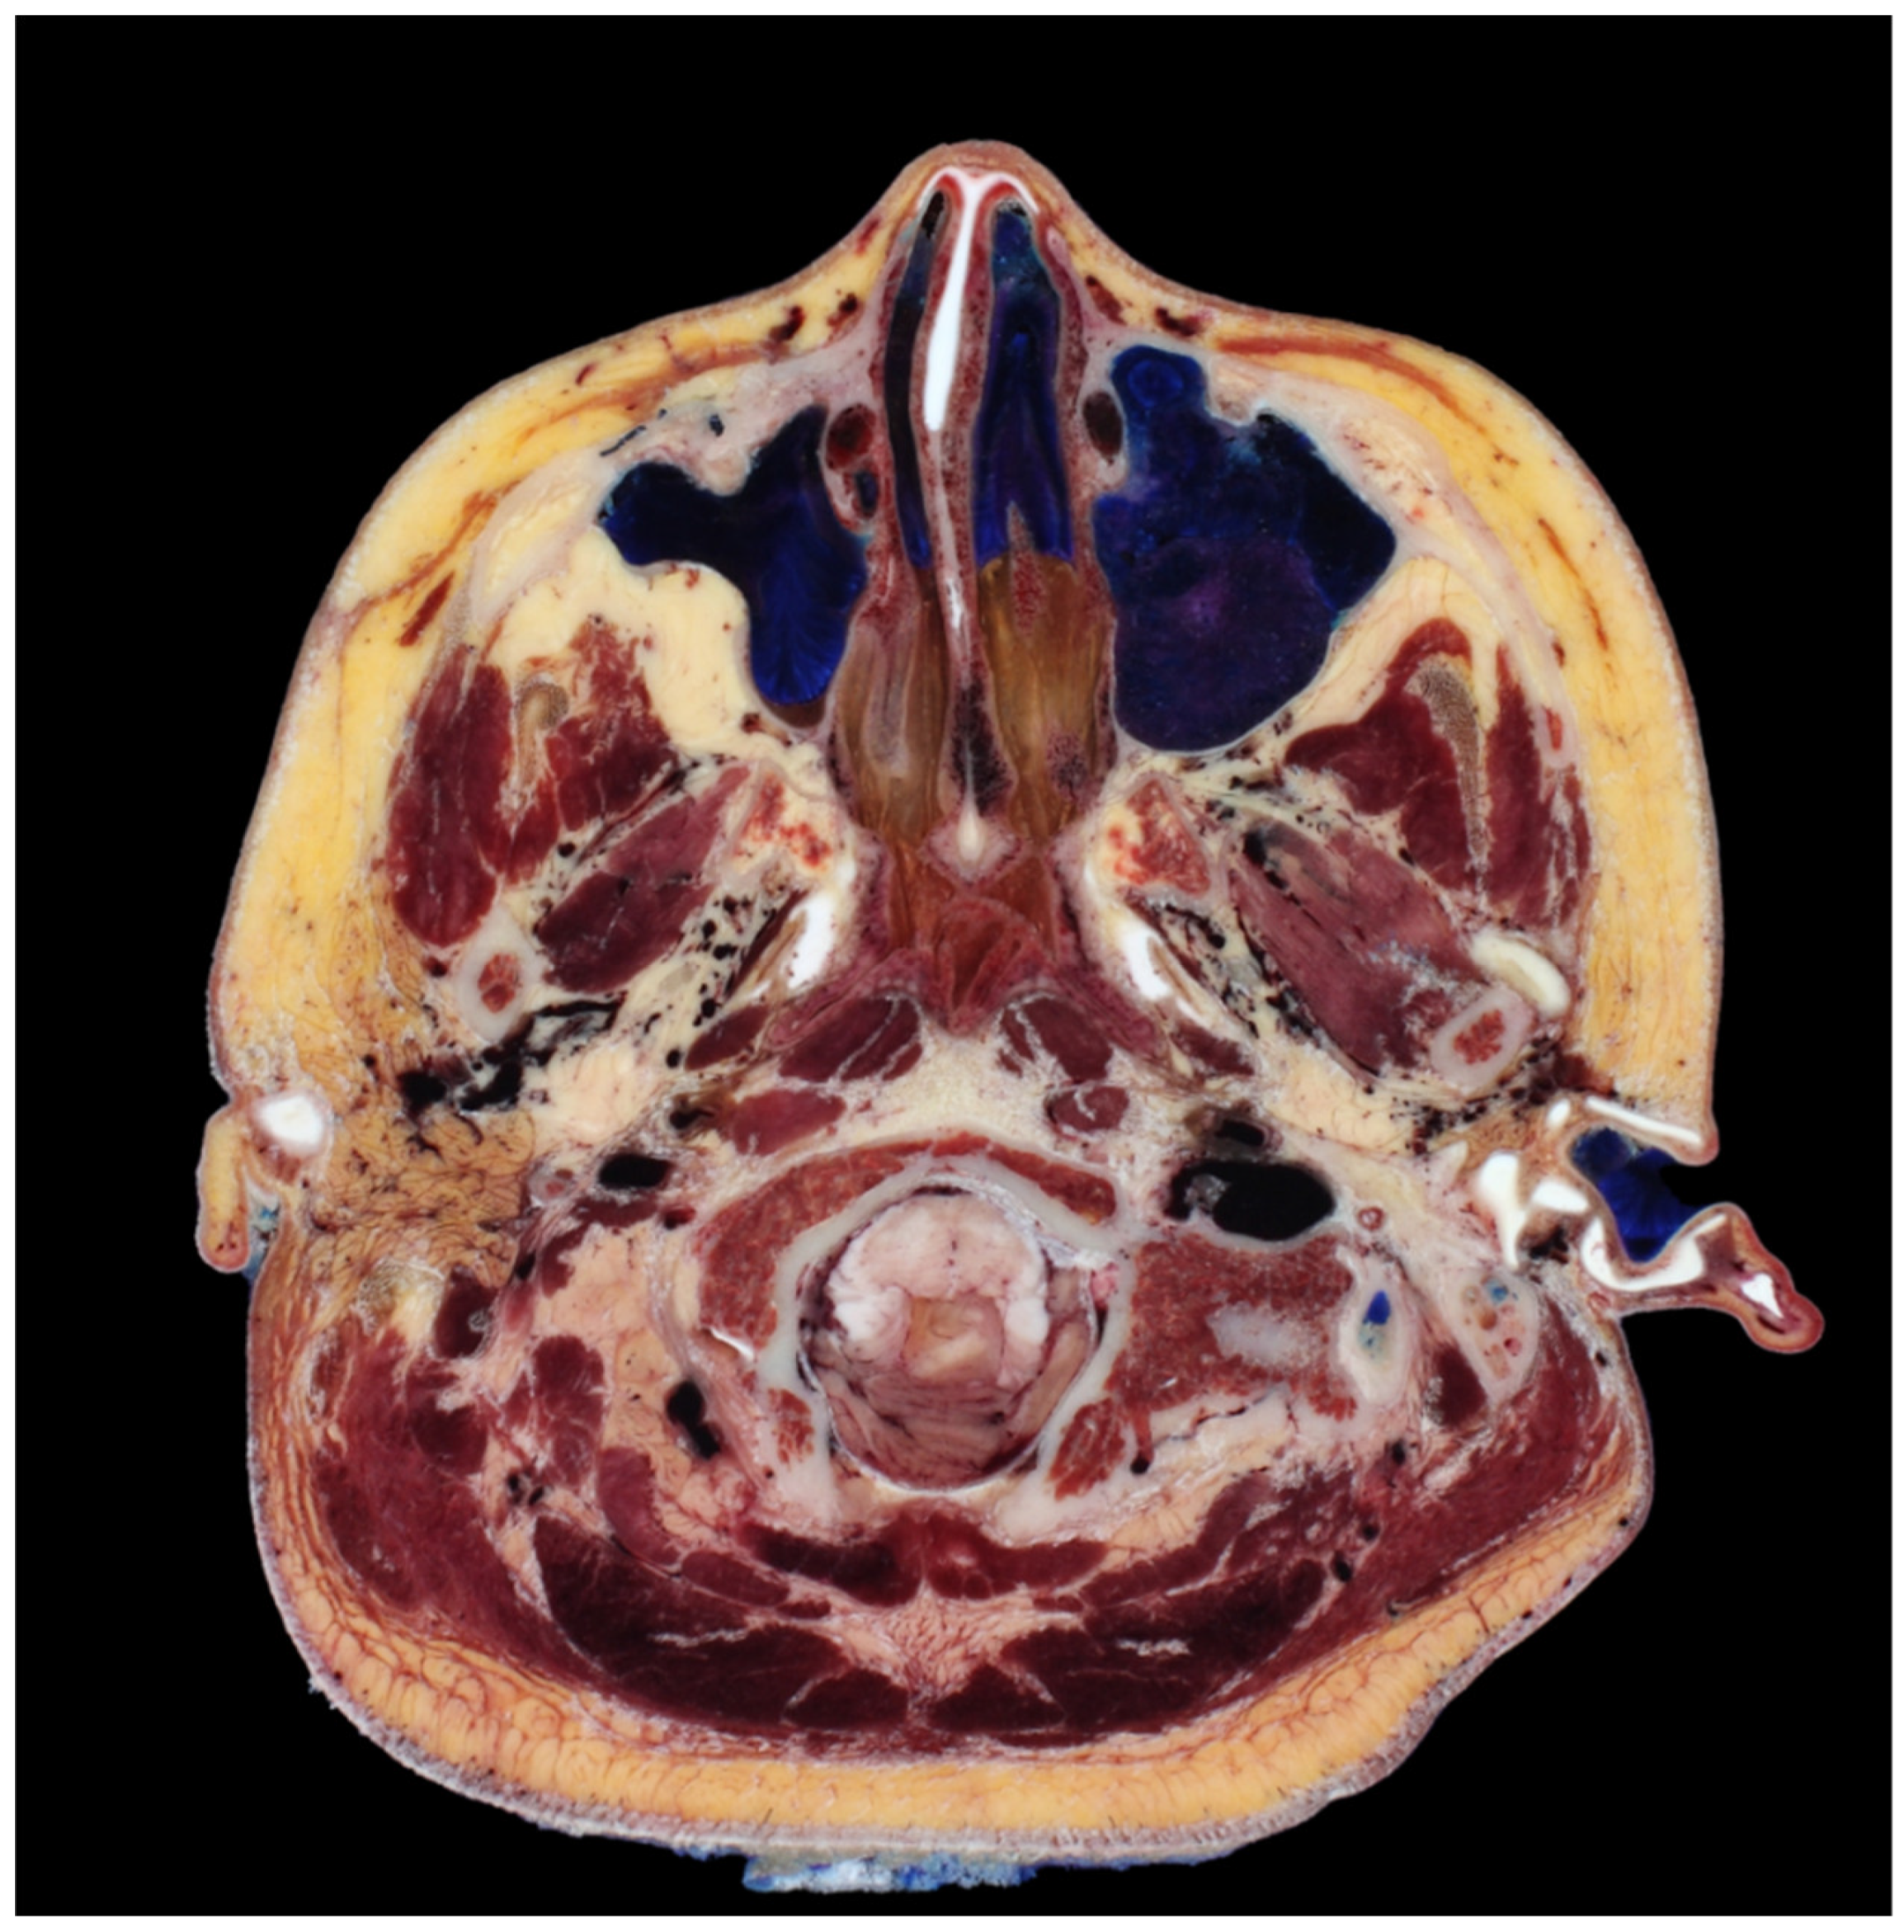

The antegrade insertion of I-type cog threads from the outer to inner direction proves insufficient in addressing lax tissues around the nose and mouth. Conventional approaches typically involve utilizing the firm tissue around the hairline in the temporal region or the anthelix between the temple and ear as fixing points, with needles or cannulas inserted inward towards the nasolabial fold. However, the angular facial structure, particularly the prominent malar eminence area that protrudes when navigating towards the anterior aspect, necessitates the bending or angling downward of needles or cannulas to surpass this region. In the context of Korean facial anatomy, a CT scan frequently reveals an angularity between the medial and lateral cheeks, approximately 70 to 80 degrees, requiring an angled approach for needle or cannula insertion to navigate between these facial compartments (Figure 5).

Figure 5.

A transverse section revealing the degree of curvature or bending between the medial and lateral cheek regions, providing insights into their structural differences. Cross-sectional head images from (Park et al., 2005) [25].